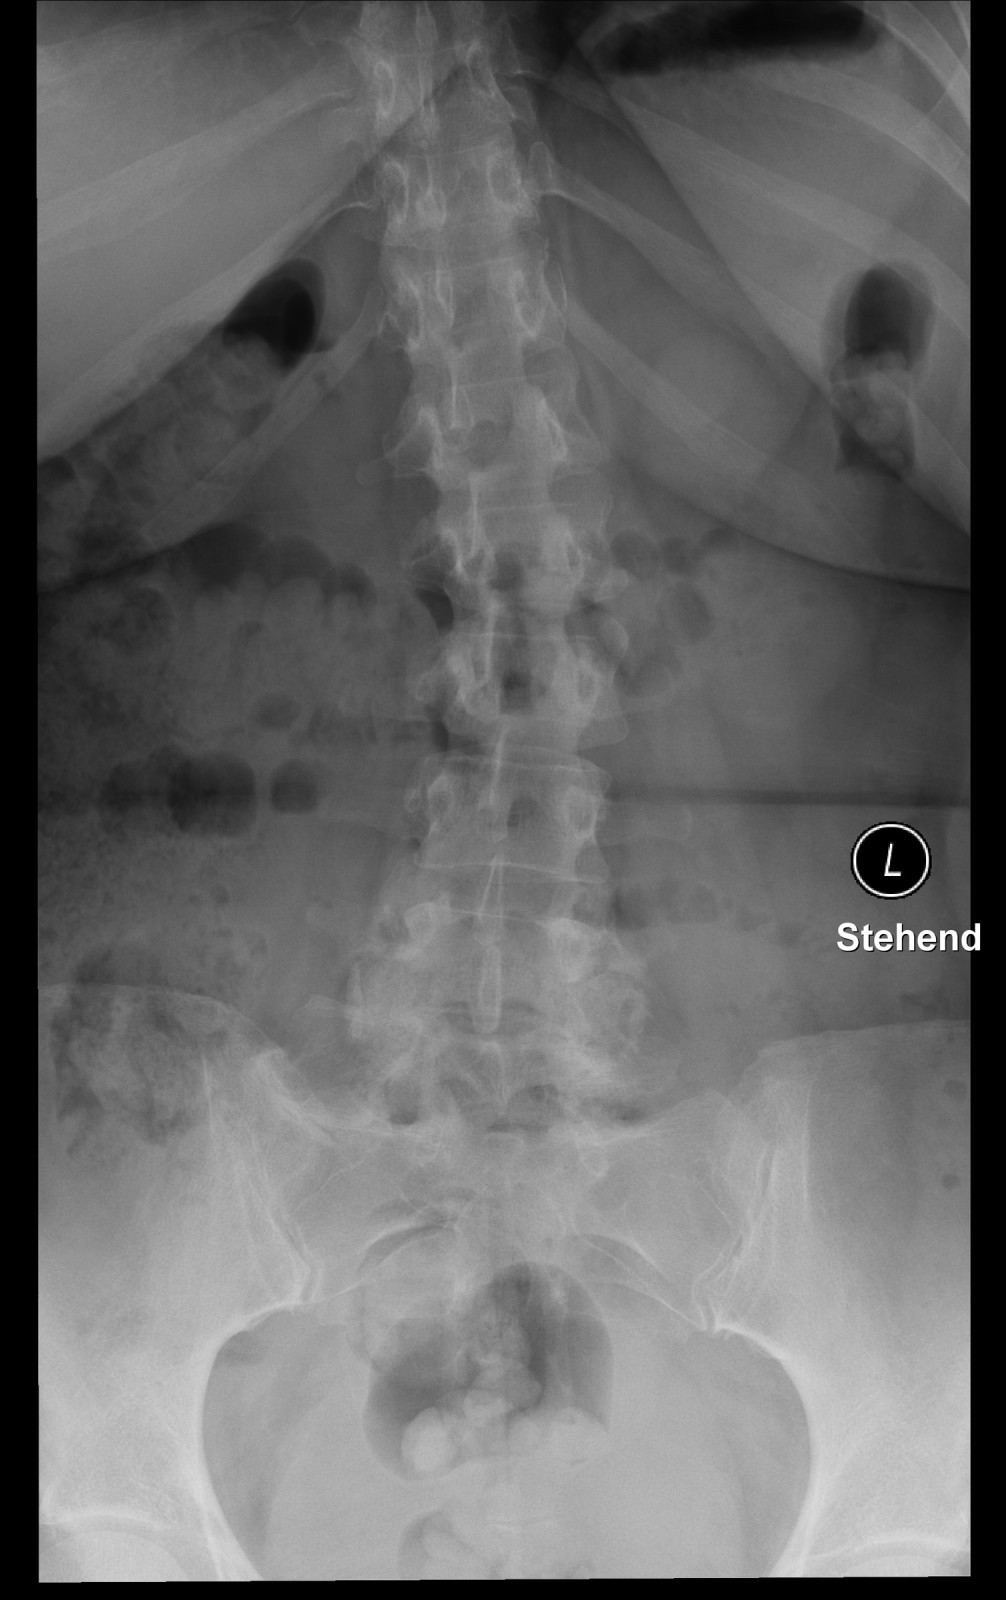

Röntgenfall des Monats Dezember 2017 mit Auflösung

45 jährige Patientin Klinische Angaben: Seit gestern tief lumbale Schmerzen ohne Trauma. Druckdolenz untere LWS und ISG bds.